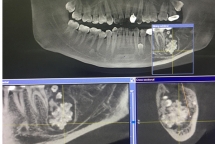

Bác sĩ gắp răng lúc nhúc trong miệng nam thanh niên Hà Nội

Nam thanh niên đi khám vì đau răng nhưng khi chụp X-quang, bác sĩ phát hiện bên dưới lợi lúc nhúc răng to nhỏ.